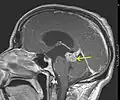

Astrocytome de bas grade dans le mésencéphale (flèche) en séquence T1 à l'IRM, vue sagittale